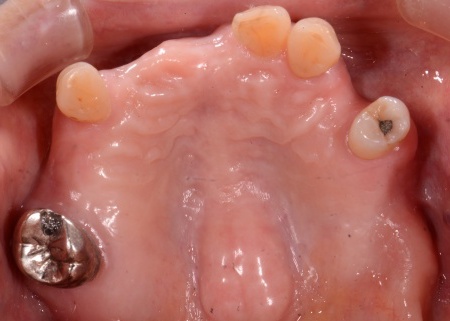

まず、上下の精密な歯型を採取し噛み合わせの位置を丁寧に確認したうえで、技工所にて入れ歯を製作しました。

後日、完成した入れ歯を装着して噛み合わせや歯ぐきの痛み、不快感がないよう細部まで調整を行い、治療を終了しました。